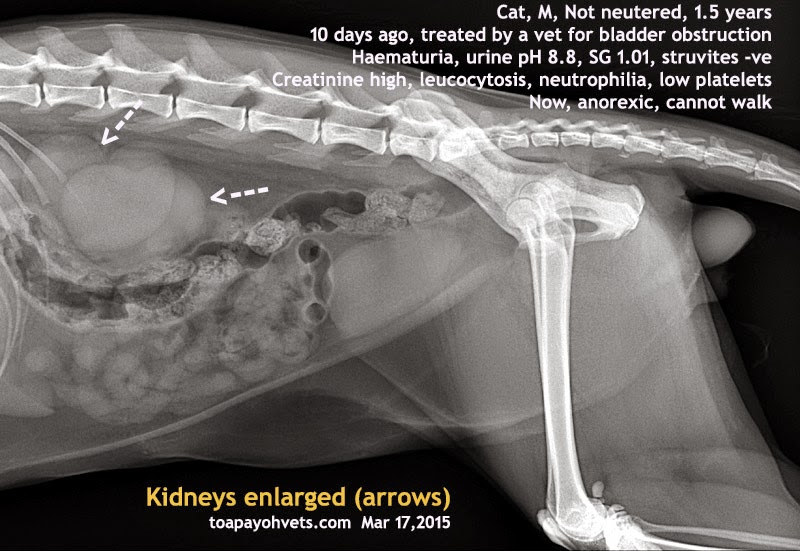

Enlarged Kidneys In Cats